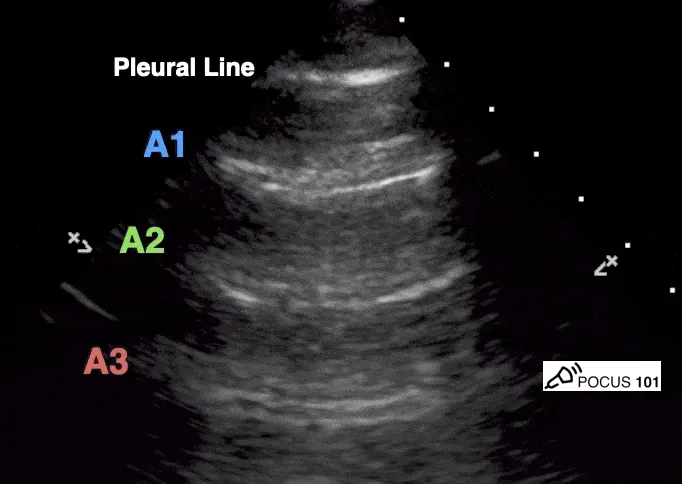

- A-lines: Horizontal, repetitive, hyperechoic artifacts arising from pleural line; indicate normal aerated lung.

- A-lines: Horizontal, hyperechoic reverberation artifacts below pleural line.

- Equidistant, parallel to pleural line.

- Signify air; normal in aerated lung with sliding.

- A-lines: Horizontal artifacts; normal lung or pneumothorax if no lung sliding.